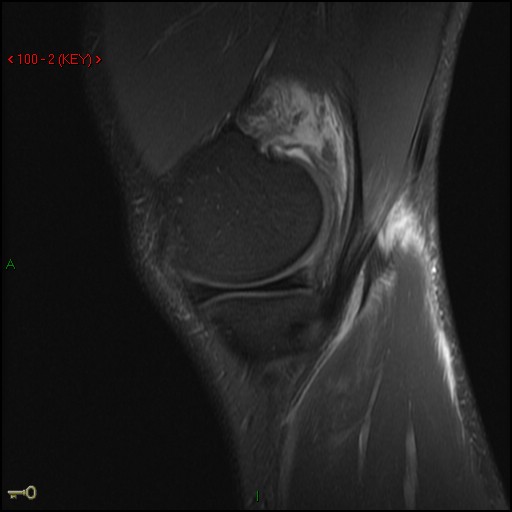

Figure 1 for case Medial head of gastrocnemius muscle ( RID2921 ) avulsion

Figure 1